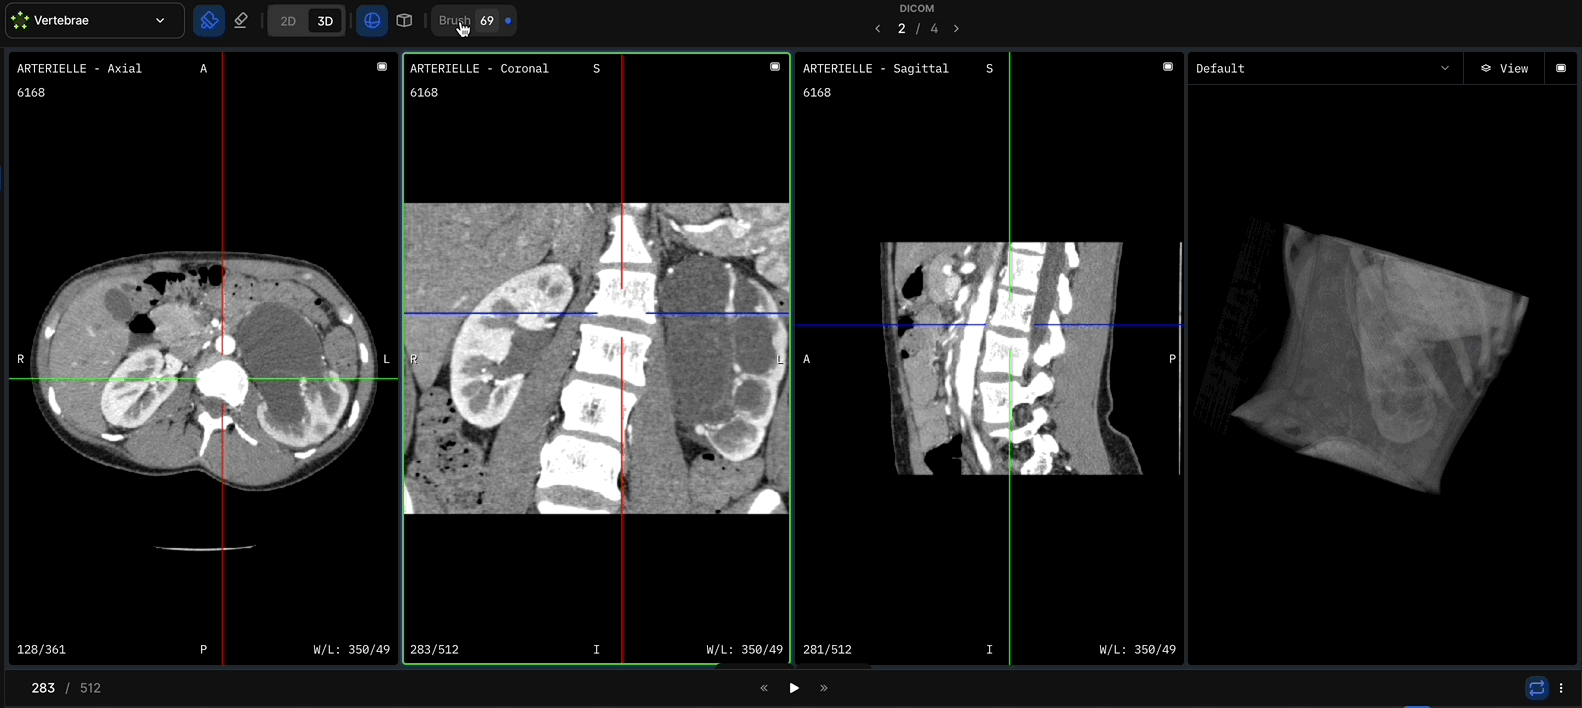

MedLabel is building the world’s most trusted source of compliant, segmented medical imaging data—automatically processed, ethically sourced from clinics, and licensed to the AI companies building the future of healthcare.

AI is only as good as its training data. MedLabel delivers compliant, auto-segmented MRI datasets—accurate, diverse, and ready to train diagnostic AI. No manual labeling. No delays. Just scalable, high-fidelity data built for the future of healthcare.

Most medical AI fails in real-world deployment due to poor data quality. At MedLabel, we address this at the source—by partnering directly with private imaging clinics to acquire real-world MRI data and transform it into automated, de-identified, and globally compliant datasets, ready to train the next generation of AI diagnostics.

High-Fidelity Automation, Not Guesswork

We use state-of-the-art AI (94.3% Dice score segmentation) to generate consistent, anatomically precise labels—no gig workers, no variability, just reproducible quality at scale.